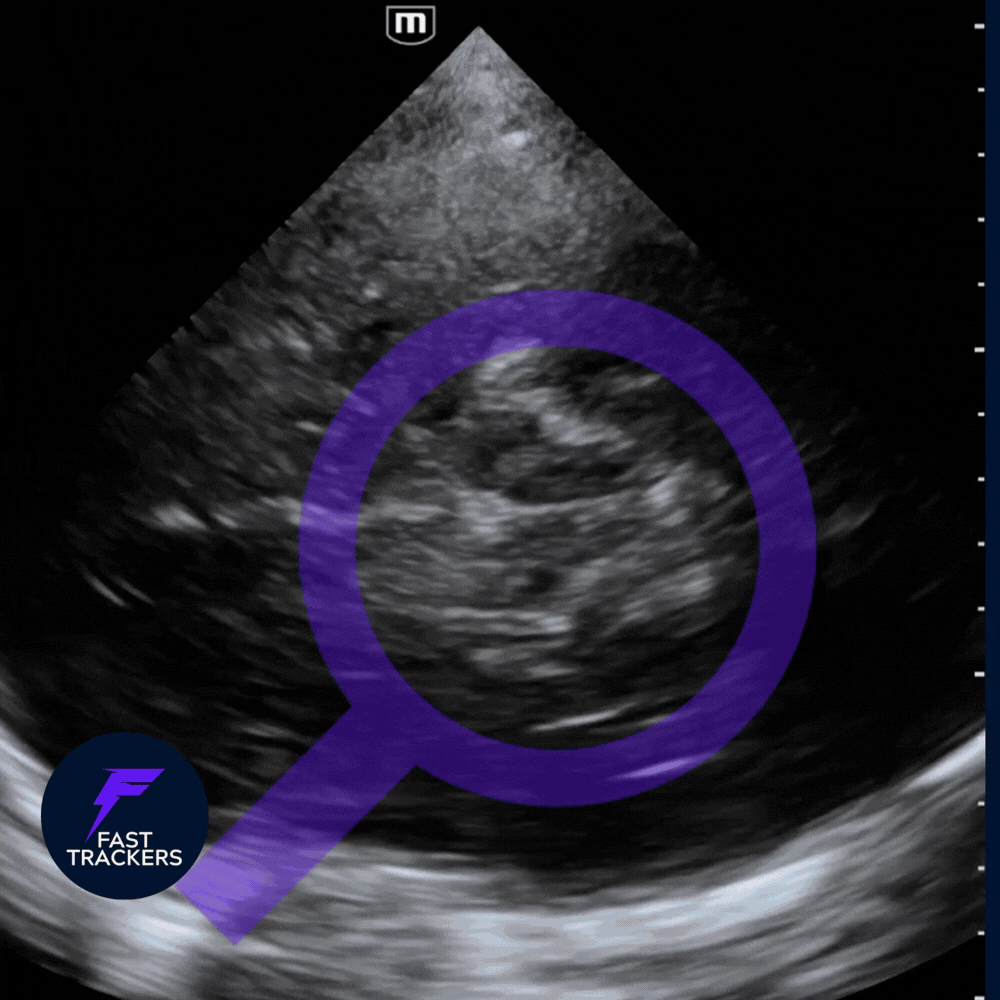

1️⃣ Étape initiale : mode B + préréglage Doppler Transcrânien (DTC / TCI)

Toujours commencer en mode B, sans Doppler.

💡 Activer le prereglage Doppler Transcrânien (DTC / TCI) pour beneficier des calculs automatiques !

-

Fenêtre temporale.

Identifier la voûte osseuse temporale controlatérale.

Au centre : structure légèrement hypoéchogène en forme de papillon/coeur → tronc cérébral.

➡️ Le tronc cérébral est ton repère anatomique.

L’ACM chemine en antéro-latéral par rapport à lui.